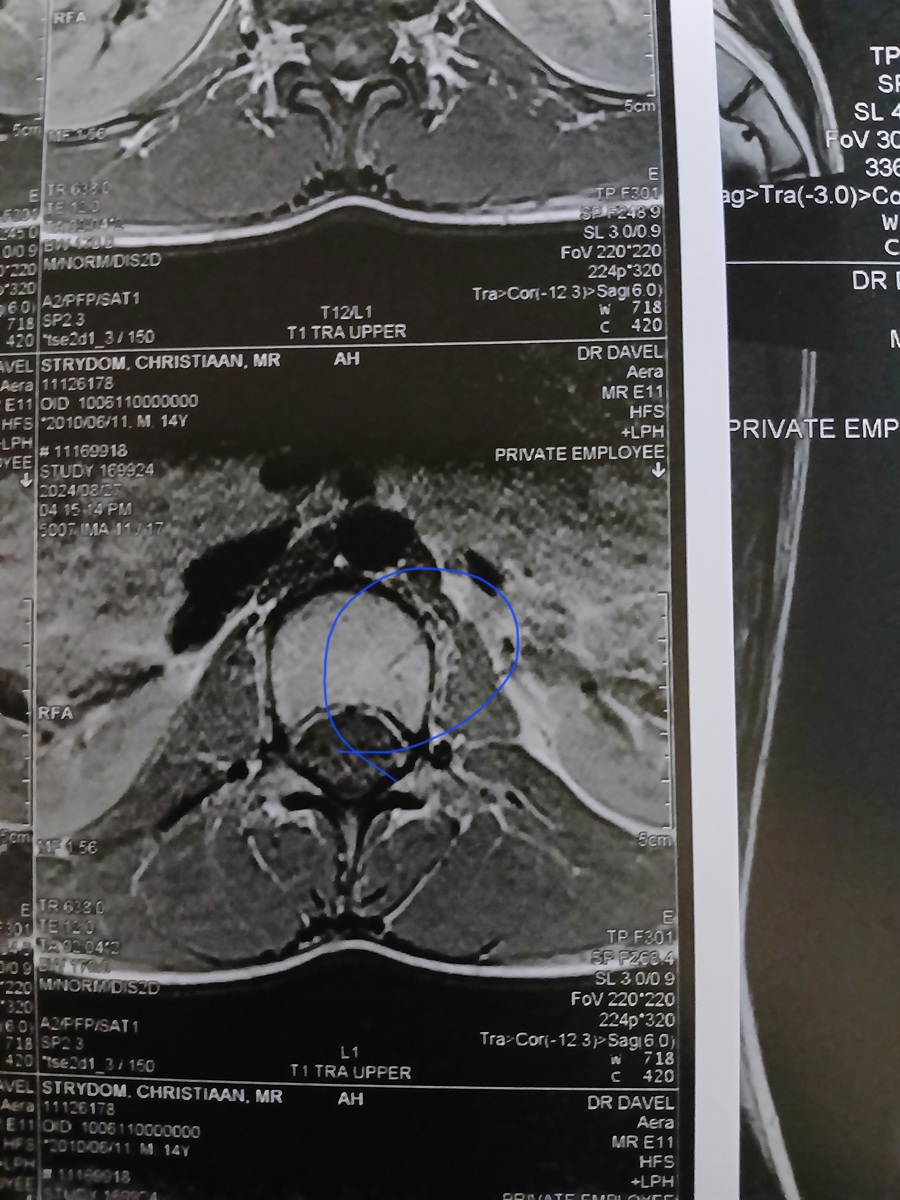

My seun Christiaan Strydom is 14 jaar oud en het die 20ste Julie 2024 ‘n beseering in ’n rugby wedstryd op gedoen. Hy het 3 van sy werwels gebreek en gekraak. Dit is sy T12, L4 en L1. Sy T12 is die ernstig gebreek maar alles is darem nog in plek wat baie goed is. Hy kry van die voorval sukkel oomblike as hy lank reg op sit of vêr of baie loop dan begin sy liggaam onbeheerlik te ruk. En dan is hy in vreeslik baie pyn en hy kan deesdae nie sy hande gebruik of loop dan nie. Hy het nog die krag in sy bene maar hy kan dit nie optel om te loop nie. Dit het in die begin so een keer ‘n week gebeur, maar die laaste twee weke gebeur dit een keer ’n dag. En dit is as of die gevoel in sy bene al hoe langer vat om reg te kom. Hy was tot vandag (12/09/2024) deur die Neurochirug dokters gesien en behandel by die Polokwane Provinsiale Hospitaal. Hulle het ons vandag verwys na die Spinale Ortopediese dokters toe wat ons eers die 1st Oktober ‘n afspraak by gekry het. Omdat ek nie ’n SASSA kaart het nie moet ons elke keer as hy hospitaal toe gaan om dokters te sien R350 betaal. Ons kon tans nie daar...